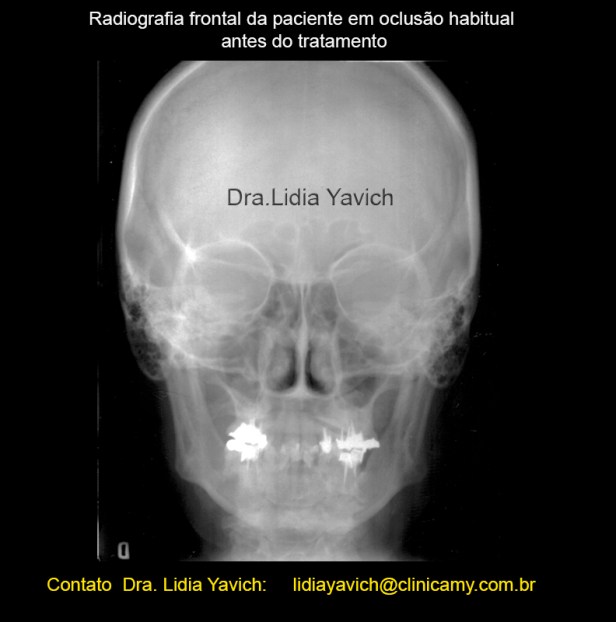

Comparação das radiografias frontais pré e após reabilitação neuromuscular fisiológica e ortodontia tridimensional.